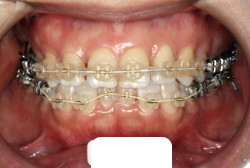

叢生(そうせい)

凸凹な歯並びのことを叢生といいます。矯正歯科に来院する患者様の主訴の中で、最も多いのが「配列の凸凹を真っ直ぐにしたい」というものです。歯の大きさと顎の大きさの調和がとれていないことが原因です。

凸凹を主体としたケースの場合、当院の平均治療期間は18ヶ月ですので、このケースは少し長めに経過しました。理由の一つは凸凹の程度がかなり重症だったと言うことですが、もう一つは、右下第2大臼歯が45度くらい前傾していたため、それを整直化させるために時間を要したと考えています。いずれにしても最終結果は大変よい状態と思います。

治療前は並びが乱れて見た目が悪いというのはもちろん問題ですが、歯科医学的に一番困るのは噛み合わせが悪いという点です。上下の犬歯(3番目の歯)は、上下的に離れた位置にあるため接触することができません。つまり歯としては存在していても、歯としては機能していないということです。